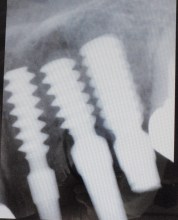

下記は右から5.0ミリ、4.5ミリ

4.0ミリのインプラントです。